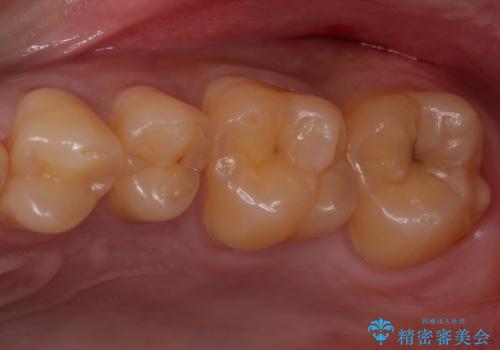

欠けてしまった奥歯 セラミッククラウンとセラミックインレーによるむし歯治療